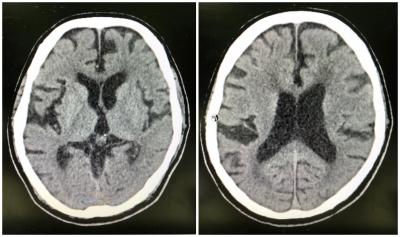

Neuroleptic Malignant Syndrome in an Elderly

Figure 1: Plain CT brain image of the patient